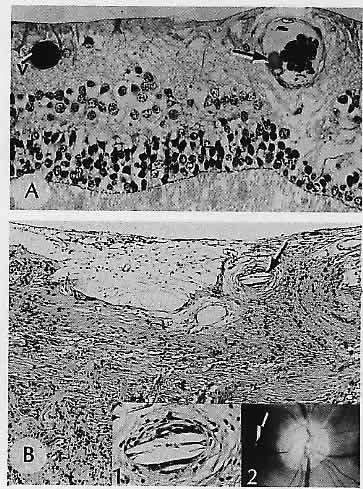

RETINAL HEMORRHAGIC INFARCTION (Fig. 8)

Fig. 8. Retinal hemorrhagic infarction. A. Central retinal vein is occluded and recanalized. The artery is identified by an internal elastic lamina (arrow). B. Hemorrhagic infarction causing disorganization of the retina in a patient with polycythemia vera and central retinal vein occlusion. Inset. Fundus following central retinal vein occlusion in an otherwise healthy 18-year-old girl; no cause for the occlusion was found. C. Sheets of blood in the inner retinal layers produce the characteristic fundus appearance. Note the preservation of the photoreceptors. D. Rubeosis iridis is present in the same patient with polycythemia vera. E. Pigment (arrows) is hemosiderin in a long-standing occlusion. (A, elastica, ×136; B, H&E, ×69; inset, fundus; C, H&E, ×69; D, H&E, × 101; E, Prussian blue, × 176)

In contrast to arterial occlusion, retinal vein occlusion is usually thrombotic and results in varying amounts of intraretinal hemorrhage. Central retinal vein occlusion can be divided into two types. The first type is nonischemic and is sometimes called venous stasis retinopathy39 (an unfortunate term, since ocular ischemia from diffuse hypoperfusion, discussed earlier, is also sometimes called venous stasis retinopathy). Nonischemic central vein occlusion is characterized by a variable number of flame-shaped and dot and blot hemorrhages but with few or no cotton-wool spots. As documented by fluorescein angiography, capillary perfusion is nearly normal, and thus the sequelae of ischemia, including iris neovascularization and neovascular glaucoma, are very rare in the nonischemic type. The visual prognosis is good.39

In younger patients, more frequently men, this condition is usually caused by venous phlebitis and runs a benign course. Clinically, it appears as disc swelling associates with venous dilatation and tortuosity and scattered intraretinal hemorrhages. Visual acuity is retained or recovered. The late sequelae include perivenous sheathing and dilated veins at the optic nerve head. In older persons, probably arteriosclerosis is the usual cause.

Ischemic central vein occlusion is also called hemorrhagic vein occlusion because of extensive retinal hemorrhage (the “blood and thunder” fundus). Numerous cotton-wool spots may be seen, but even if they are obscured by the hemorrhage, fluorescein angiography helps to document the extensive capillary closure and ischemia. Iris neovascularization is frequently associated and characteristically occurs between 6 weeks and 6 months (so-called 90-day glaucoma).39 With either type of vein occlusion, hemorrhage into the macula can result in permanent visual loss.

Histologically, central retinal vein occlusion appears acutely as hemorrhagic necrosis, with massive hemorrhage involving all layers of the retina (Fig. 9). The hemorrhage may also extend under the internal limiting membrane, separating it from the underlying nerve fiber layer. Cytoid bodies and optic nerve head edema may be present. Whether complete or “impending,” a thrombus occurs in the central vein,40although as Hayreh subsequently noted,39 only one of Green's cases was nonischemic histologically. All the rest had neovascularization of iris, optic disc, or both, sometimes with inner retinal ischemic atrophy.

Fig. 9. Hemorrhage within the nerve fiber layer (arrow) tends to “track” along the nerve fibers, producing a flame-shaped hemorrhage observed clinically. An accumulation of blood in the potential space between the internal limiting membrane (ilm) and the nerve fiber layer produces submembranous intraretinal hemorrhage, which is generally restrained from entering the vitreous compartment by the strength of the overlying thick basement membrane. Pockets of blood accumulating within the bipolar cell layer or between Henle's fibers (photoreceptor axons) of the extramacular outer plexiform layer produce the dot and blot hemorrhages seen clinically. (H&E, × 115)

Later in the evolution of the occlusion, exudates may occur in the outer plexiform layer. Other late changes include disruption, gliosis, and hemosiderosis of the retina. The retinal blood vessel walls can be markedly thickened. The thrombus is organized and may be recanalized.40